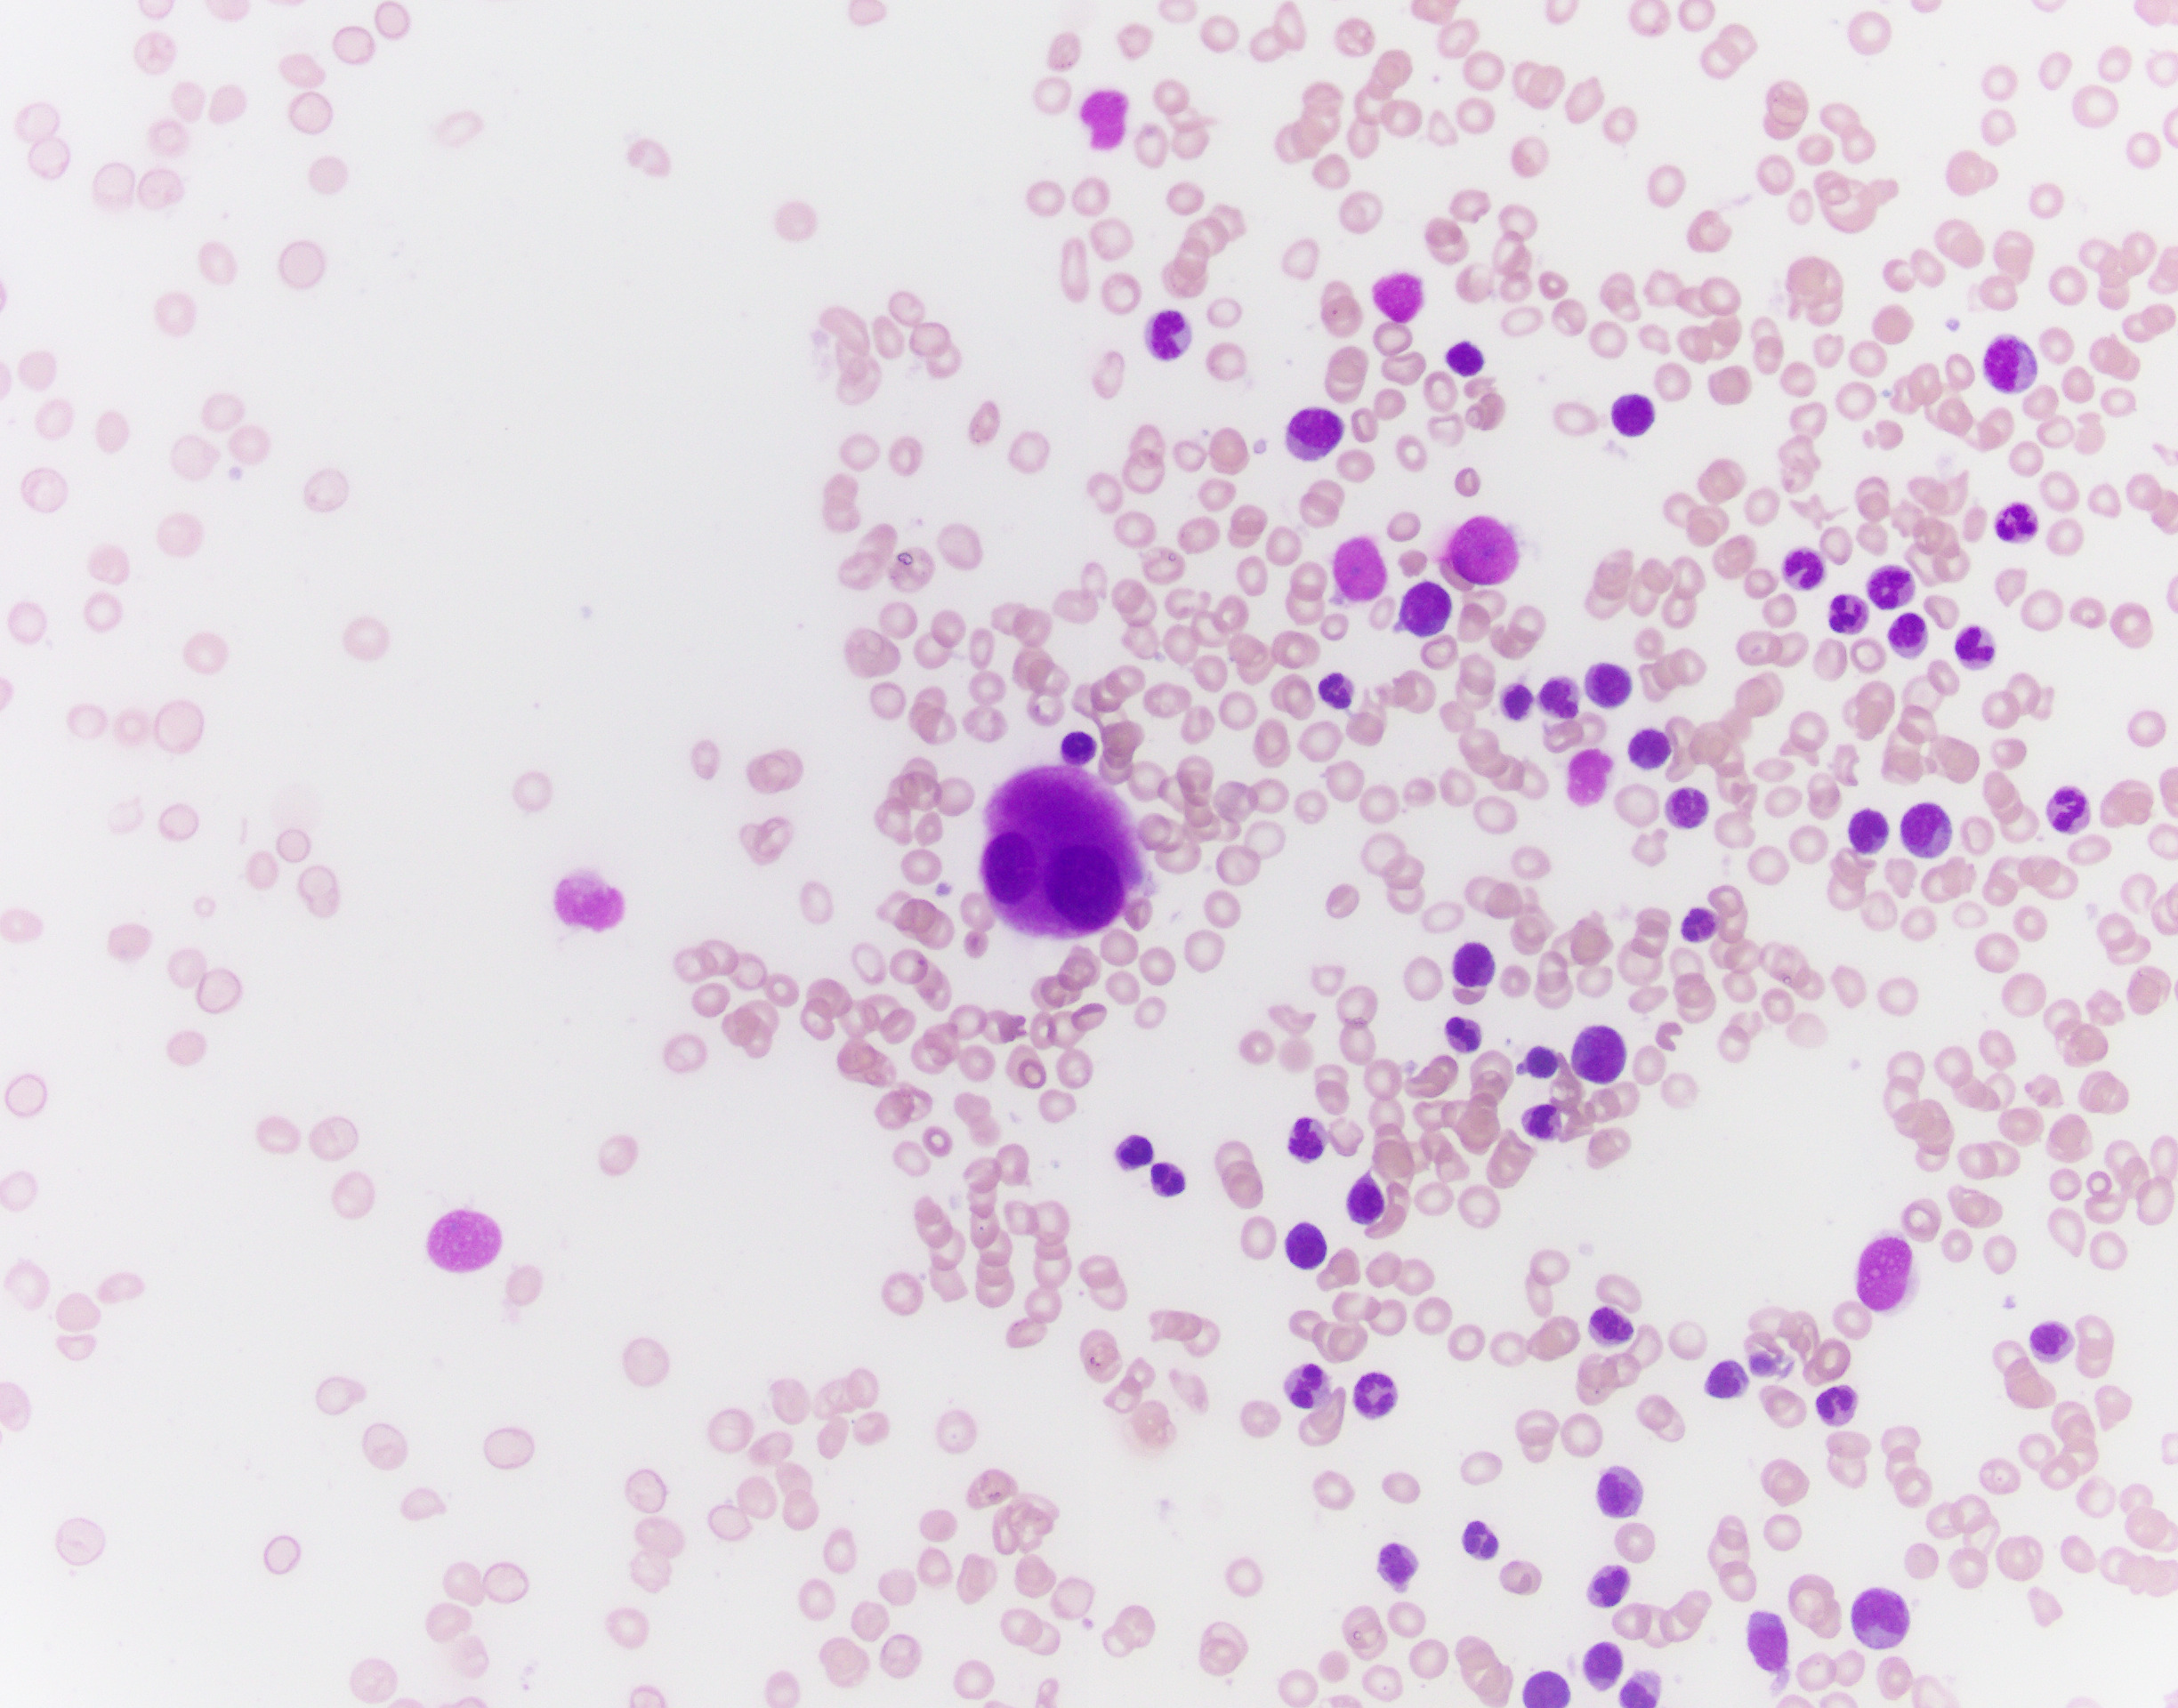

The patient is a 76-year-old male with anemia (Hgb 8.6) and thrombocytopenia (15,000/microliter). Of note, serum copper levels are low. Photomicrographs of the bone marrow aspirate and biopsy are provided.

Copper deficiency is notorious for being a mimicker of MDS, and supplementing copper and observing the patient's CBC and possibly repeating a biopsy may be necessary in this patient. While definitely a possibility, this case is not classic for pure copper deficiency. Thrombocytopenia is less common, and the classic morphologic findings in copper deficiency are dysplasia in the erythroid lineage with cytoplasmic vacuoles in the erythroid and granulocytic lineages.